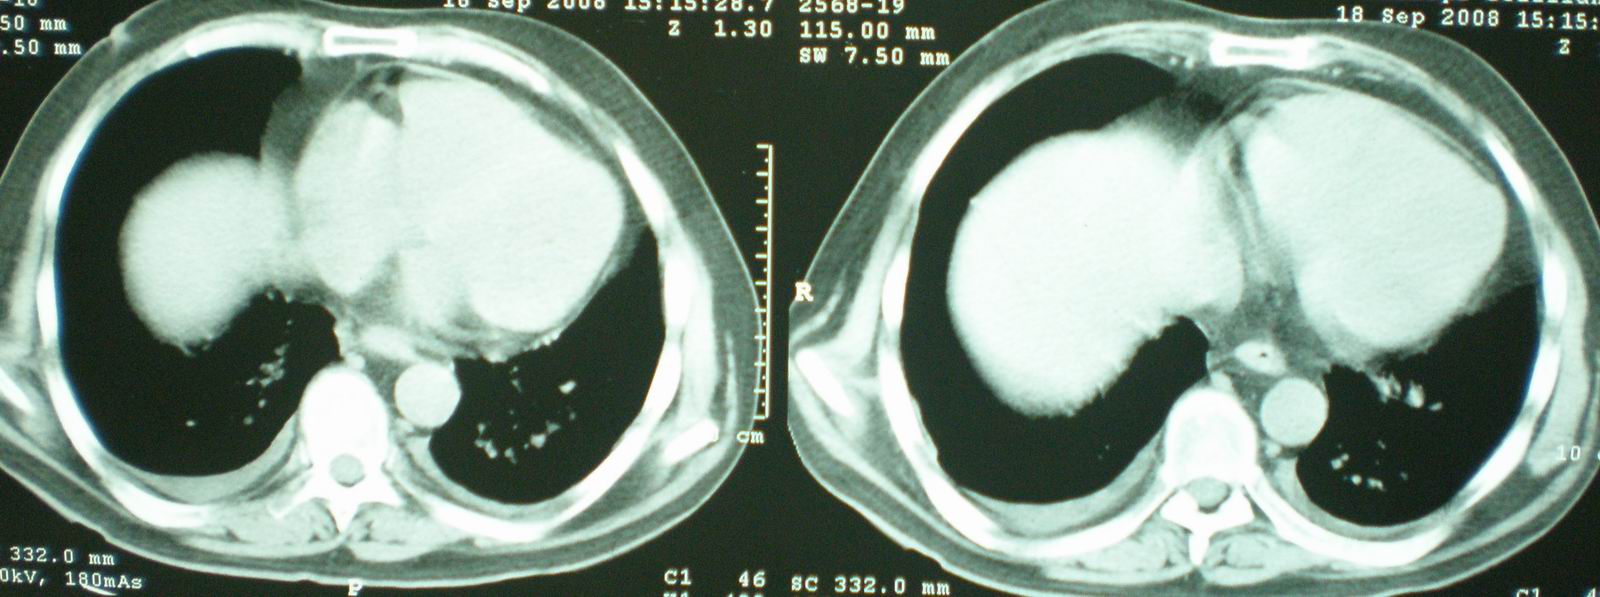

病人资料:男,52岁,因体癣股癣等皮肤病行激素治疗,因突然大剂量减药而起病,病情危急,9月8日曾在上级医院住院治疗,9月18日复查了ct片,相关检查及住院小结以图片资料上传。

2008年11月18日今天的ct片

[face=宋体]显然上级医院进行了抗结核,抗真菌,抗炎等治疗,目前病人肺内病灶基本消失,双侧胸腔积液,右侧积液量有吸收,抗结核一个多月,现在病人疑问,结核的诊断是否有疑义,抗结核是否继续,因为那个毕竟副作用大。[/face]

我仔细看了下病人的出院小结,当时情况危急,诊断里有1型呼衰。心包周围的是脂肪密度。结合三次ct扫描的图象分析,个人认为:1、病人目前肺部病灶基本消失,双侧胸腔内少量积液,抗结核治疗才一个多月,就算是结核,抗结核治疗有效果,为何效果如此好,一点纤维灶的痕迹都没有呢,再就是患者做过气管镜检查及活检、痰检均未找到结核的证据。所以不支持结核的诊断。

2、结合现在的ct片,考虑:肺水肿及真菌感染,双侧胸腔积液。